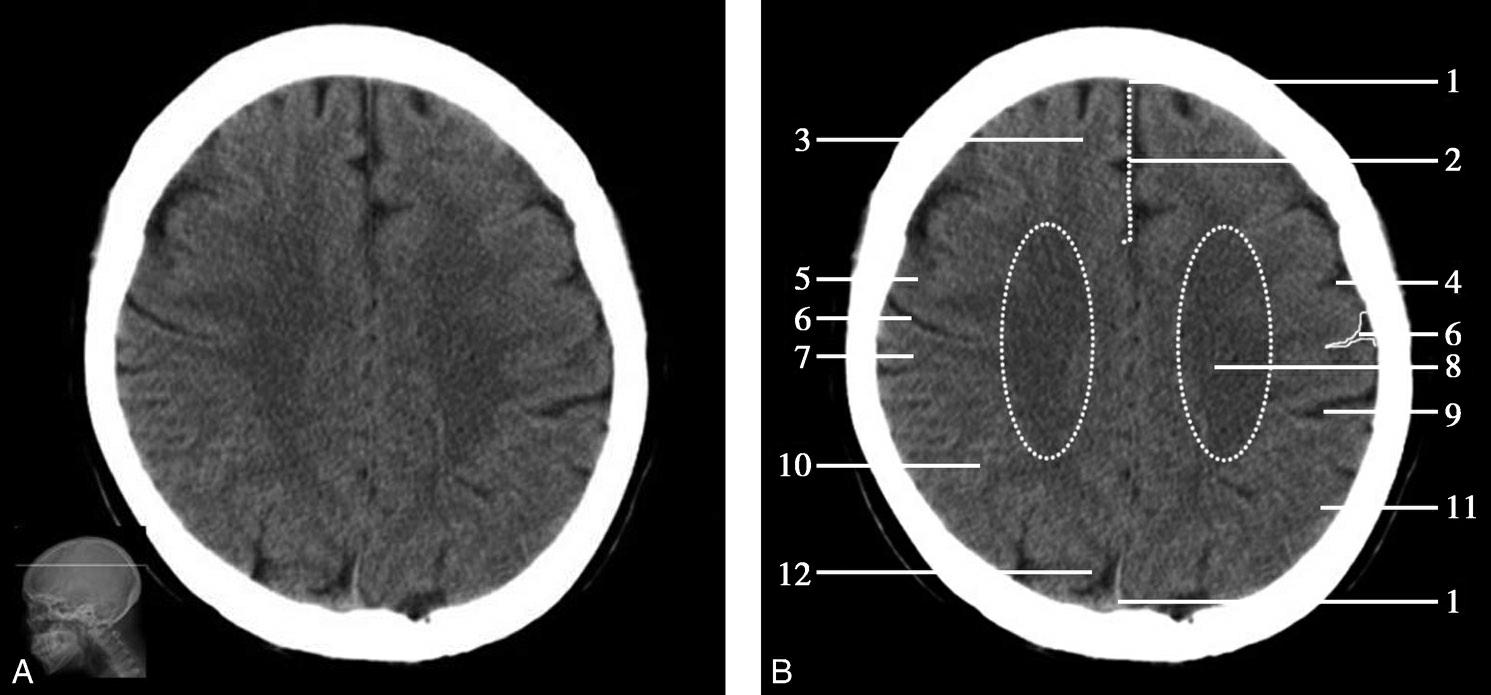

重要结构:尾状核体部、侧脑室体部、放射冠、额叶、顶叶(图1-2-34~图1-2-36)。

图1-2-34 尾状核体部层面

A.横断面;B.横断面标注

1.上矢状窦;2.大脑镰;3.额叶;4.颞肌;5.扣带回;6.胼胝体;7.透明隔;8.中央前沟;9.中央前回;10.中央沟;11.中央后回;12.中央后沟;13.尾状核体部;14.岛盖;15.放射冠;16.脉络膜丛;17.侧脑室体部;18.顶叶;19.顶枕沟;20.枕叶

Alberta卒中项目早期CT评分(Alberta stroke program early CT score,ASPECTS)是一种评价急性缺血性卒中患者大脑中动脉供血区早期缺血性改变的简单、可靠、系统化的方法,是常用的脑卒中评定量表之一,可对缺血性病变快速进行半定量评价,有助于判定溶栓效果和远期预后。该评分主要基于CT平扫,具体分区如下(图1-2-76)所示,即选取大脑中动脉供血区2个层面。分区后共10个区域,每个区域记1分。评分时任何区域只要有低密度灶,则扣除该区域得分。正常脑ASPECTS评分为满分(10分),若MCA供血区广泛梗死累及全部区域时,则ASPECTS评分为0分。

图1-2-76 ASPECTS评分脑组织分区

A.在基底节层面(即丘脑和纹状体平面),分为各级分支M 1 、M 2 、M 3 、岛叶(缩写I)、豆状核(缩写L)、尾状核(缩写C)和内囊(缩写IC)后肢等7个区域;B.在基底节以上层面(基底节层面上2cm),包括M 4 、M 5 和M 6 。